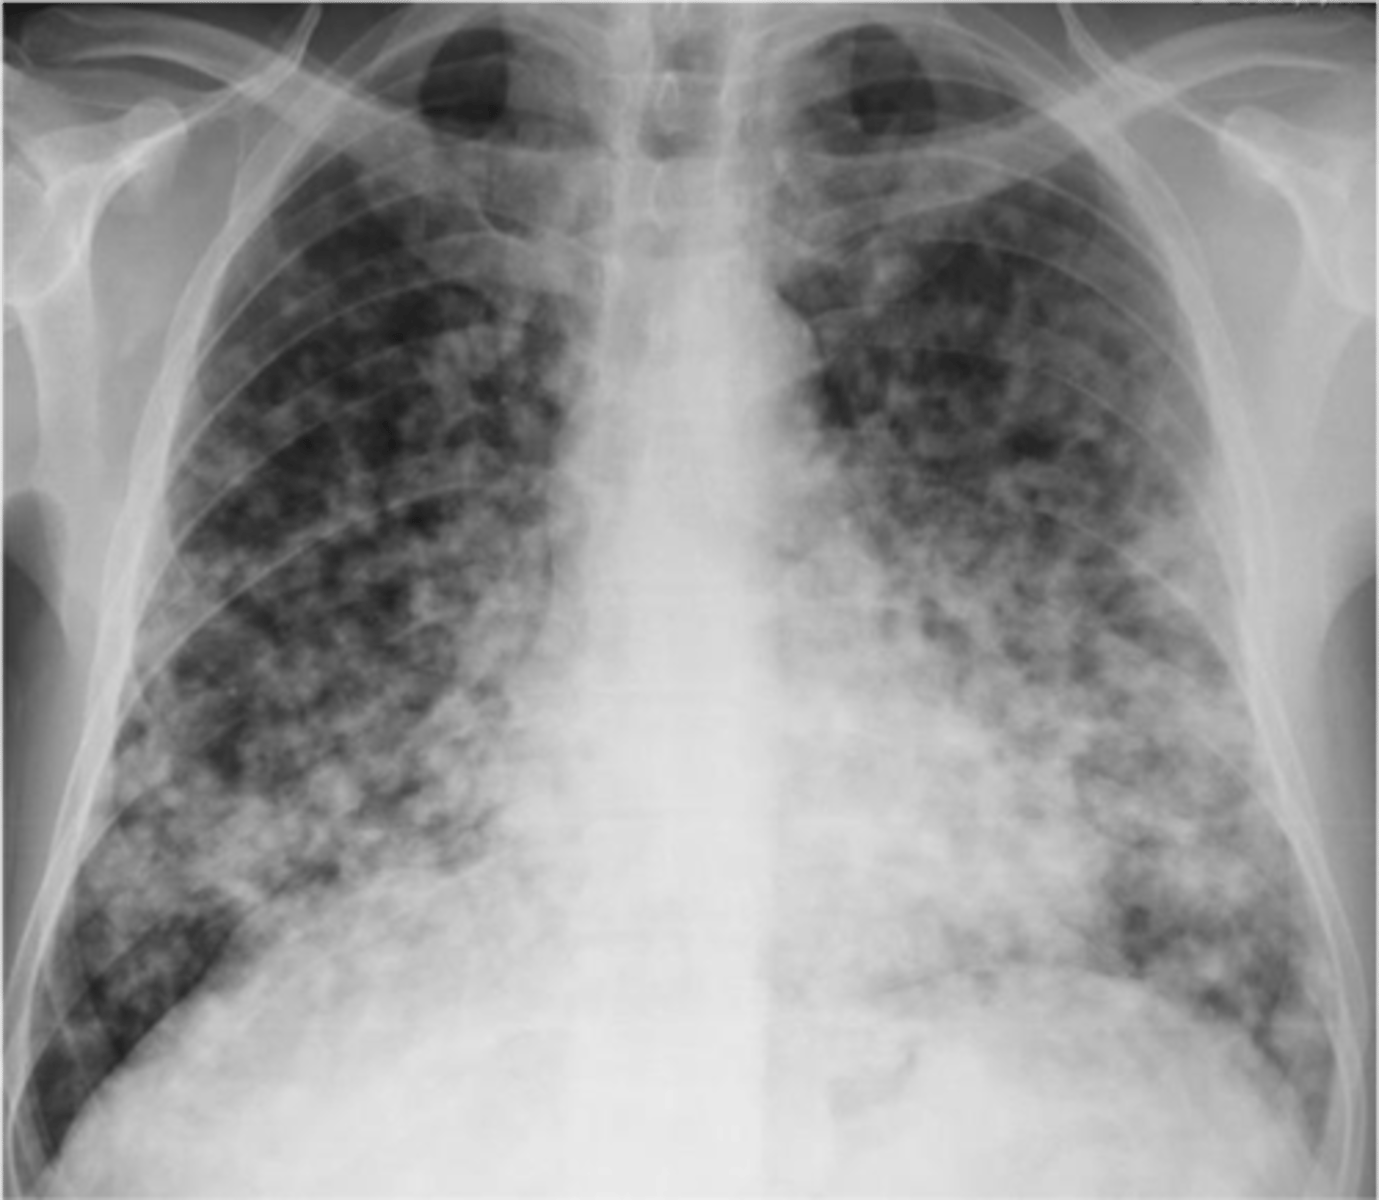

Reticulonodular interstitial infiltrate

Multiple nodules- metastatic